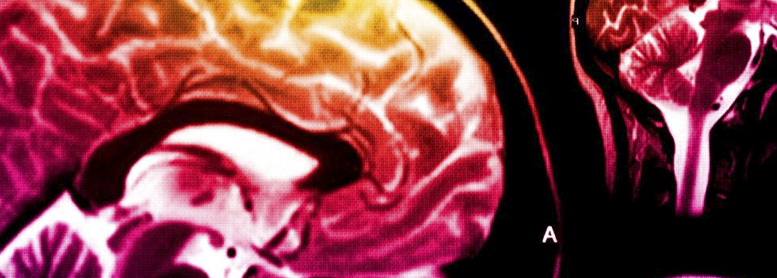

Expert Postgraduate in Neuroimaging, EXP

Etiquetas: Neuroimagen